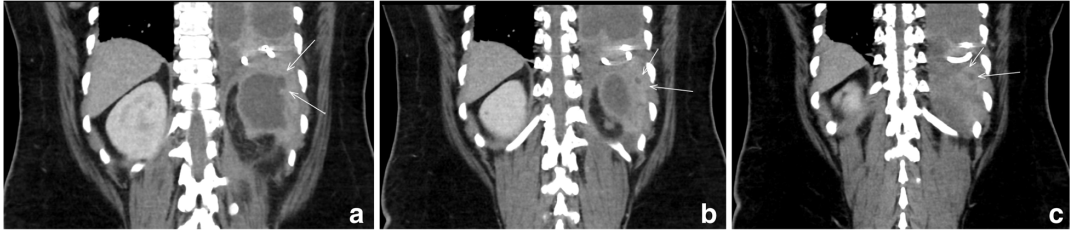

在有房颤的情况下,用组织纤溶酶原激活剂(tPA)和脱氧核糖核酸酶(DNAse)行胸膜腔内溶栓治疗72小时。纤溶治疗后无明显改善,患者被带到手术室进行大口径胸导管放置和电视胸腔镜手术(VATS)剥离左内脏胸膜。胸膜液培养出奇异变形杆菌(图1),因此患者接受了进一步的影像学检查,以确定主要来源。腹部/骨盆的计算机断层扫描(CT)显示左肾上极有一个复杂的囊性病变,与同侧横膈膜相通(图2,3)。尿液分析不明显。在脓肿内放置引流管,囊肿液培养也显示奇异变形杆菌阳性。

图3. 计算机断层扫描结果显示患者的腹部的连续冠状横切面,白色箭头表示从肾囊肿到膈肌的后上方延伸的通道